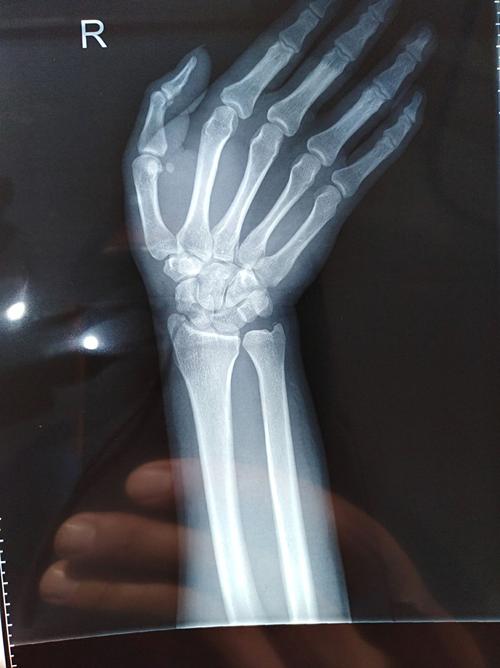

x光照片手

x光照片手,x光照片

永城市中心骨科,手外科为你解忧愁

手x光片

右手x光片

手x光

正常右手x光片图片

正常右手x光片